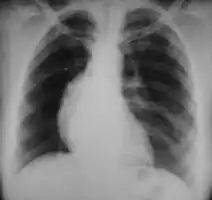

• Lymphadenopathy: the most common symptom of Hodgkin is the painless enlargement of one or more lymph nodes.[14] The nodes may also feel rubbery and swollen when examined. The nodes of the neck and shoulders (cervical and supraclavicular) are most frequently involved (80–90% of the time, on average).[14] The lymph nodes of the chest are often affected, and these may be noticed on a chest radiograph.[14]

After Hodgkin lymphoma is diagnosed, a person will be staged: that is, they will undergo a series of tests and procedures that will determine what areas of the body are affected. These procedures may include documentation of their histology, a physical examination, blood tests, chest X-ray radiographs, computed tomography (CT)/Positron emission tomography (PET)/magnetic resonance imaging (MRI) scans of the chest, abdomen and pelvis, and usually a bone marrow biopsy. Positron emission tomography (PET) scan is now used instead of the gallium scan for staging. On the PET scan, sites involved with lymphoma light up very brightly enabling accurate and reproducible imaging.[29] In the past, a lymphangiogram or surgical laparotomy (which involves opening the abdominal cavity and visually inspecting for tumors) were performed. Lymphangiograms or laparotomies are very rarely performed, having been supplanted by improvements in imaging with the CT scan and PET scan.